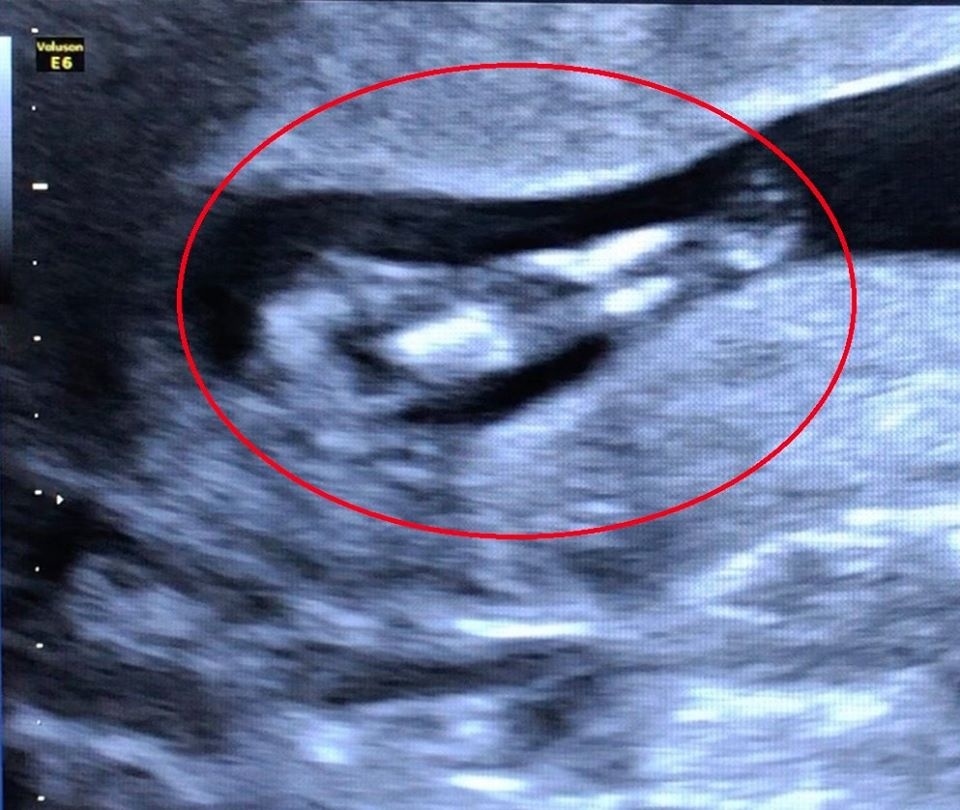

Qua hình ảnh siêu âm, bác sĩ phát hiện thai nhi có hai chân dính vào nhau giống như đuôi cá, bất thường ở bàng quang và hệ tiết niệu.

Bệnh nhân 32 tuổi đến thăm khám định kỳ với tuổi thai 11 tuần 5 ngày. Qua kết quả hình ảnh siêu âm cho thấy thai nhi hai chân dính vào nhau giống như đuôi cá, bất thường ở bàng quang và hệ tiết niệu, dây rốn một động mạch.

Hình ảnh ghi nhận trường hợp thai nhi mắc hội chứng người cá trên siêu âm. Ảnh: BVCC.

Sau khi phát hiện, bác sĩ tiếp tục thực hiện các xét nghiệm tầm soát bất thường nhiễm sắc thể, đồng thời tư vấn cho bệnh nhân về tình trạng dị tật của thai nhi và tiến hành chấm dứt thai kỳ.

BSCKII Lương Kim Phượng, Trưởng khoa Chẩn đoán hình ảnh, cho biết trẻ bị hội chứng người cá chỉ sống được từ vài giờ đến vài ngày sau sinh. Thậm chí, trẻ có thể ngưng sự sống khi chưa sinh do biến chứng liên quan đến sự phát triển và chức năng của thận. Vì vậy, trong quá trình mang thai, chị em cần tuân thủ lịch khám thai định kỳ tại các cơ sở y tế chuyên khoa.